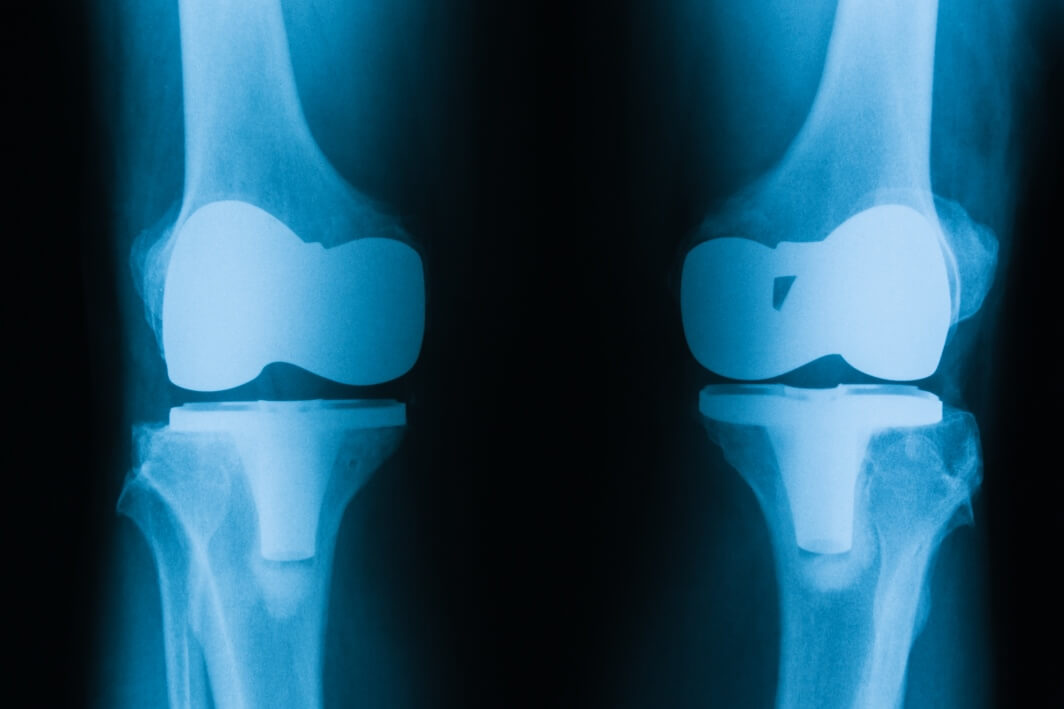

Regain Mobility and Live Pain-Free with KneeCares